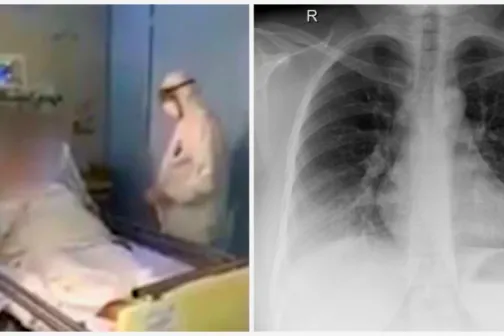

Imagine 08/03/2020 -22:53 Sănătate Video! Primele imagini din boxa în care este internată pacienta cu coronavirus revenită din Italia

Imagine 08/03/2020 -22:14 Sănătate Coronavirus: epidemia din Italia a atins astăzi un nivel record, 1.200 de cazuri noi într-o singură zi